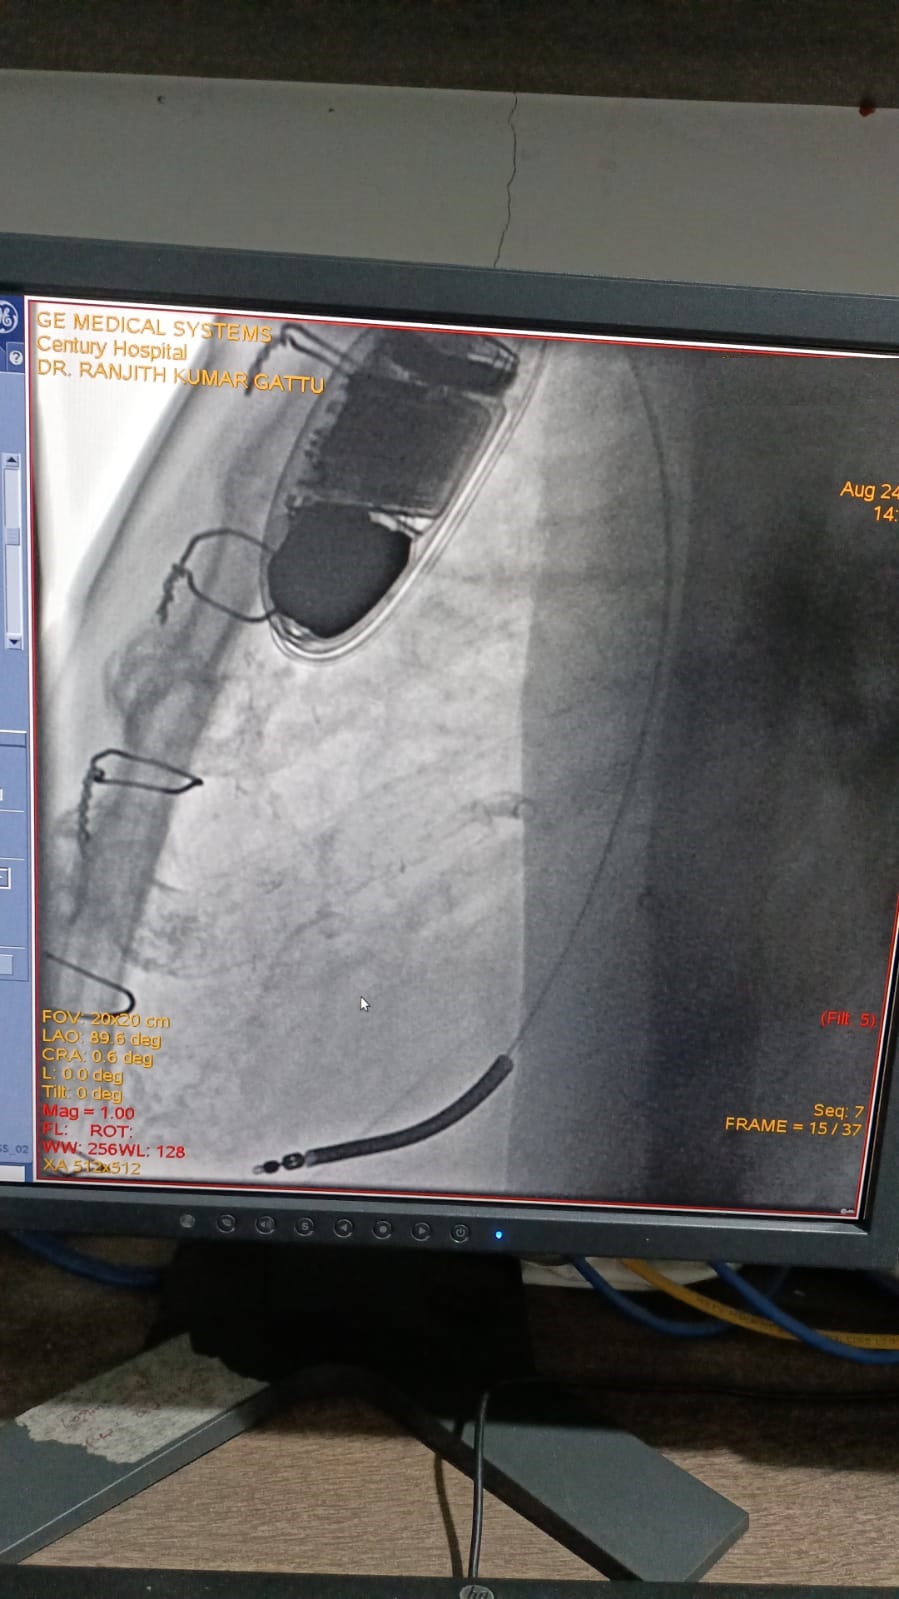

Catheter ablation of arrhythmias